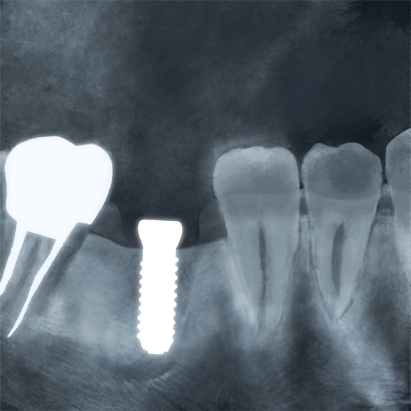

術後レントゲン写真

-